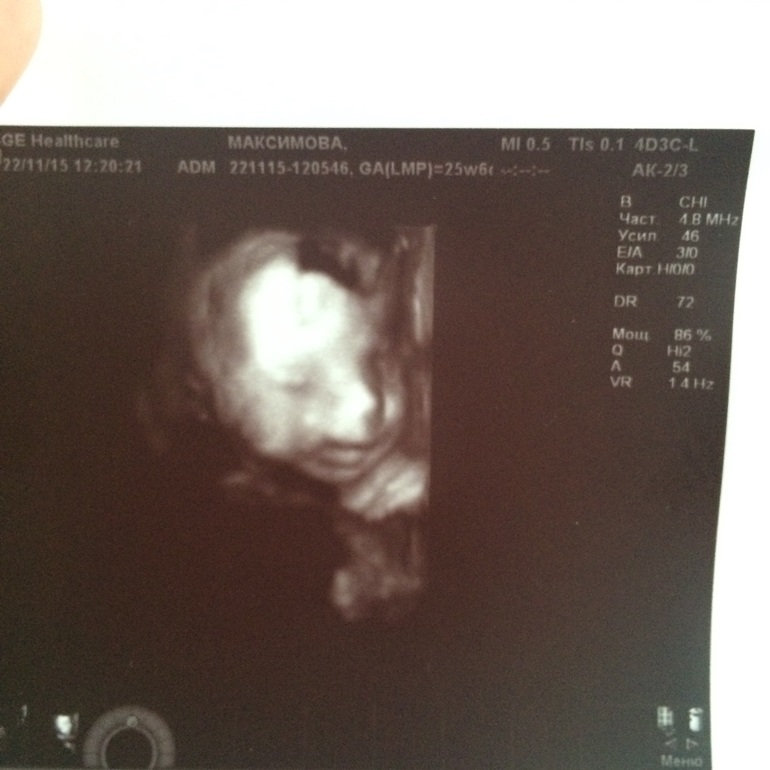

УЗИ, КТГ, доплерХодили сегодня на 3д узи. Разочаровалась, как-то его быстро сделали, хотя впринципе все посмотрели. Полиночка весит уже 800г, соответствует своему сроку. На шее лежит пуповина, сидит пока на попе. Похожа вроде на старшую дочку :) фото под катом :)

Ну и сдувшийся после дня лежания дома животик. 25.6 недель. Прибавка 7кг